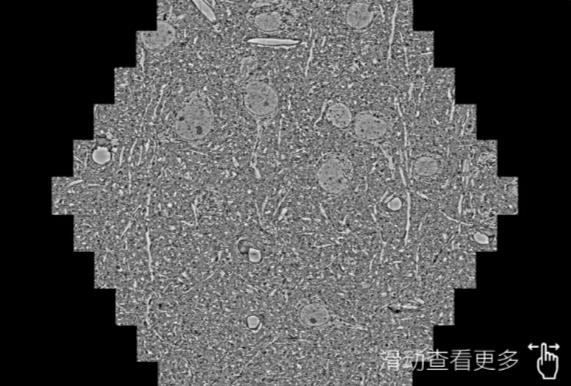

鼠脑切片。左图使用伊春蔡司伊春扫描电镜MultiSEM706对165μmx143pm面积区域成像,耗时仅需1.5秒。右图为鼠脑切片中30μm区域放大效果。样品由芝加哥大学B.Kasthuri提供。